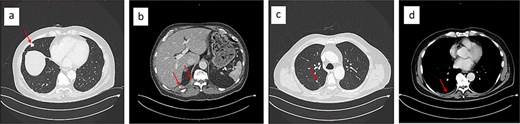

Upon rituximab-bendamustin treatment completion, the CT-thorax/abdomen revealed complete NHL remission but demonstrated features consistent with thoracic EHE. The CT displayed multiple pulmonary nodules on the right, with partially calcified lesions, including subpleural (Fig. 2a), paravertebral, and intercostal lesions (Fig. 2b). Additionally, there were increasing nodular changes along the oblique fissure and a pleural effusion (Fig. 2d).

Chest CT showing partially calcified stable 15 × 13 mm subpleural lesion in the lateral middle lobe (a), a paravertebral mass at the level of the T11/12 vertebral foramen, and an intercostal lesion at the level of T10–12 (b). Nodular changes along the oblique fissure (c), and a mild right-sided pleural effusion (d).